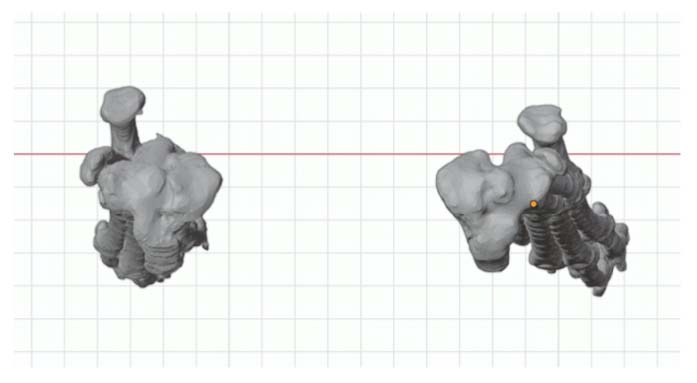

Correct the right femur angular limb deformities with a mid-diaphyseal oblique closing-wedge ostectomy centered at the CORA of the femoral deformity, which is located within the mid-diaphyseal (do not recommend a traditional distal femoral ostectomy (DFO) as this would result in a significant lateral femoral translation in this specific case). The trochlea is arthritic and hypoplastic, but not overtly deformed. In this case, a traditional block or wedge trochleoplasty is recommended rather than a patellar groove replacement (PGR). In addition, a corrective de-torsional tibial osteotomy has been recommended, as a tibial tuberosity transposition (TTT) is unlikely able to compensate for a torsion of this magnitude.

CT CAD-based surgical plan.

Although not required for Cassidy, a patellar groove replacement (PGR) would be another option for those cases with significantly malformed femoral trochlear grooves and/or progressive femoropatellar degenerative joint disease later in life.